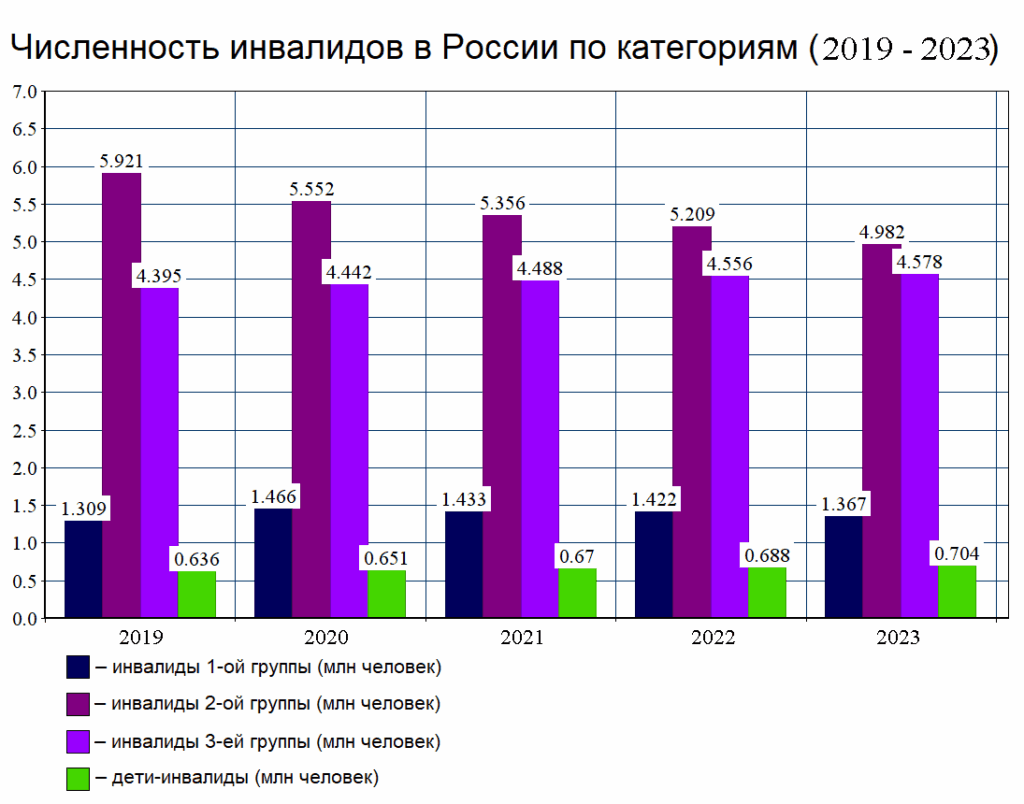

Проблемы с суставами представляют огромную опасность для людей. В 94% случаев инвалидности причиной является развитие артрита и артроза.

Официально в России ежегодно больше 4,5 миллиона человек становятся инвалидами из-за болезней суставов! Об этом молчат и бессовестно скрывают существование эффективного средства для решения этой проблемы.

Не ждите, когда случится непоправимое! Хватит наполнять карманы фармацевтов и горе-врачей, увеличивая статистику инвалидов России! С помощью средства Алтайский сбор вы избавитесь от проблем с суставами раз и на всю жизнь!